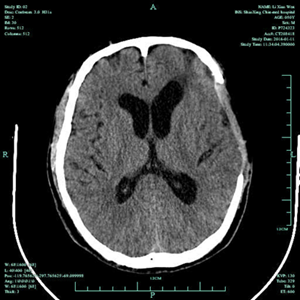

2015年11月12日,49岁的李先生在工地干活时不慎从高处坠落,致头部受伤,当时情况危急,由120送至我院,查头颅CT提示颅内广泛硬膜下出血、脑挫伤、脑疝形成,属于重度颅脑损伤,生命危急。我院神经外科王风永主任当机立断,在全麻下给患者施行左侧额颞顶硬膜下血肿清除+去颅骨瓣减压术,手术顺利。术后在ICU及十二病区全体医护人员的精心治疗和护理下,患者逐渐康复,语言表达、肢体活动、生活自理方面均恢复良好,术后一月顺利出院,并建议患者在家修养一段时间后,尽早返院再行颅骨缺损修补手术。

受伤术后